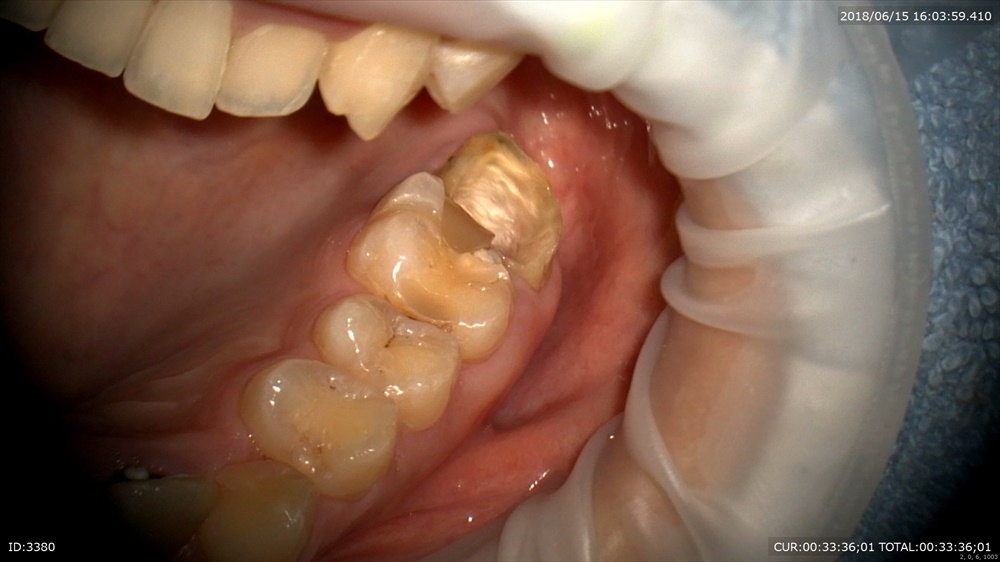

今日も似たような症状の方のHさんが

今年2月。

「痛い。腫れがある。」

診断はパーフォレーション。根っこに穴が開いていました。

通常は抜歯になります。この方は強く保存治療を望みました。根管治療時にMTAにてリペアを施しました。術後4ヶ月。安定しています。

ですので本日土台と仮歯を入れました。